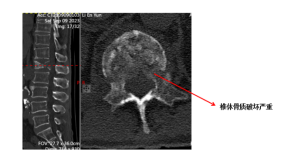

南京江北医院李涛院长会诊仔细检查和鉴别诊断后,确诊李老先生喉癌转移到椎体导致了骨质破坏,随后又进行了进一步的检查;磁共振显示李爷爷的腰1椎体骨质破坏,发生了病理性骨折,向后方压迫脊髓神经,这正是李老先生腰痛加下肢无力、麻木的根源。